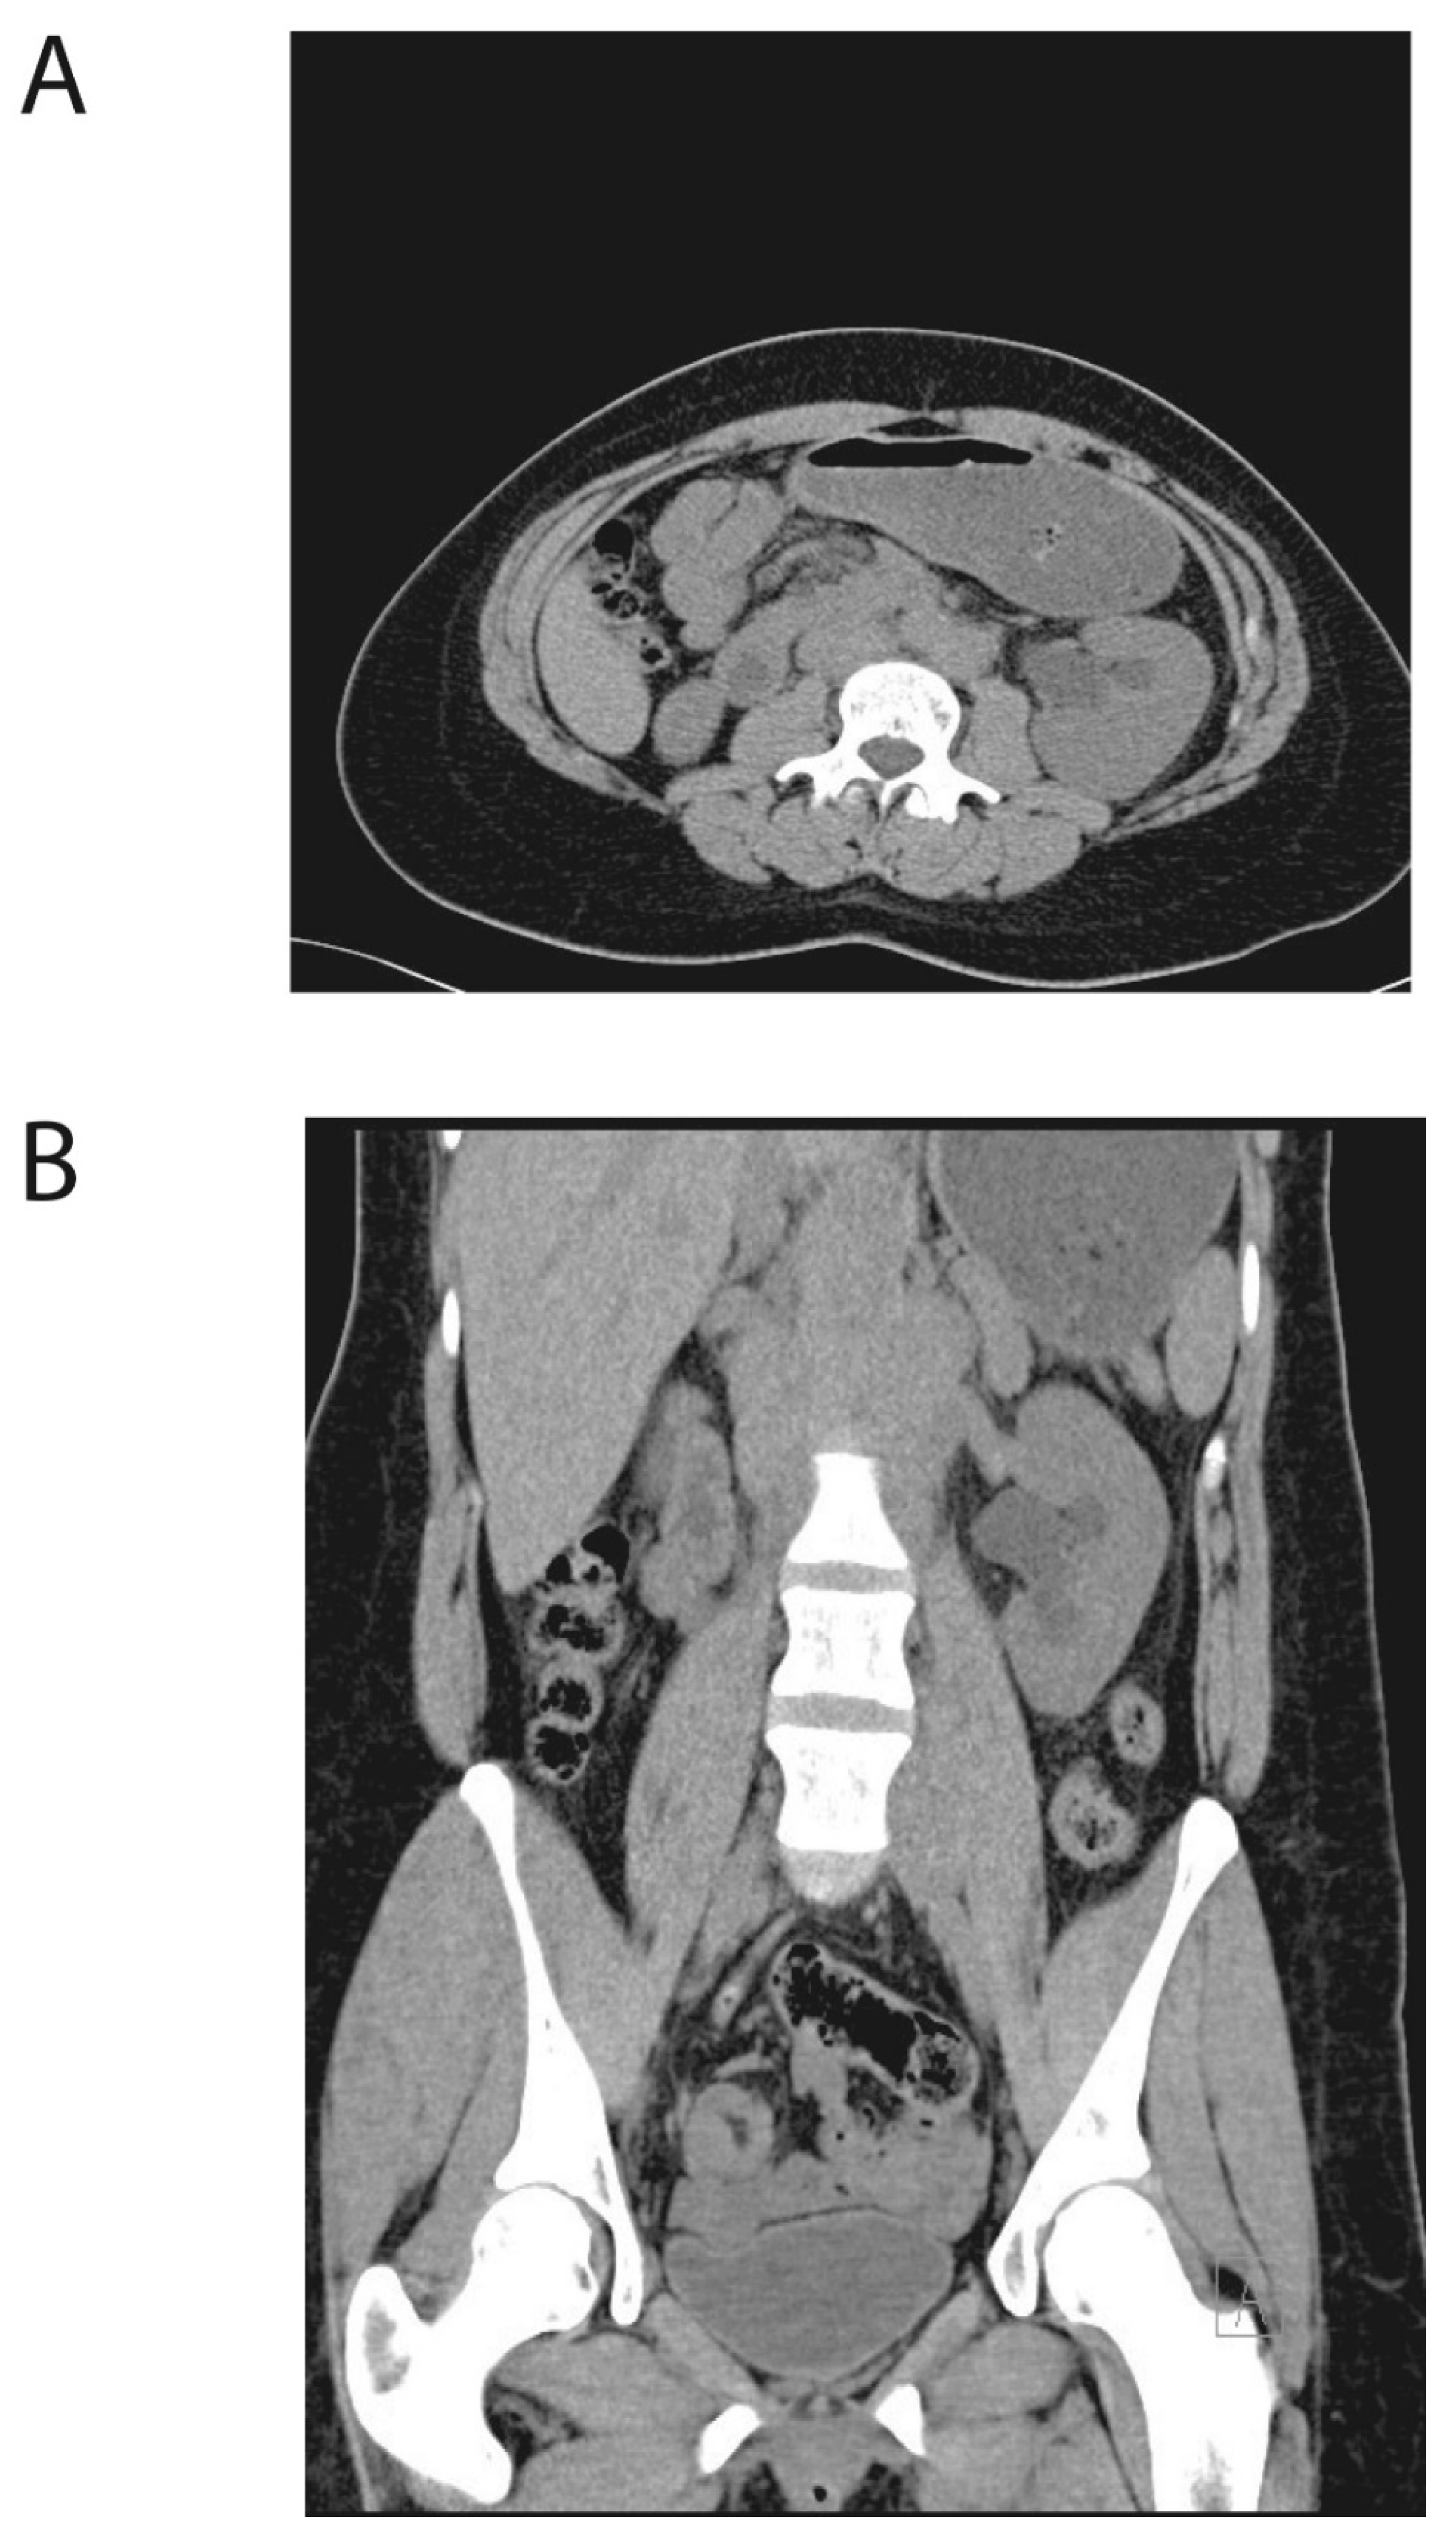

Kidney Failure and Abdominal Discomfort as Initial Signs of Extramedullary Acute Myelogenous Leukemia

2. Case Presentation